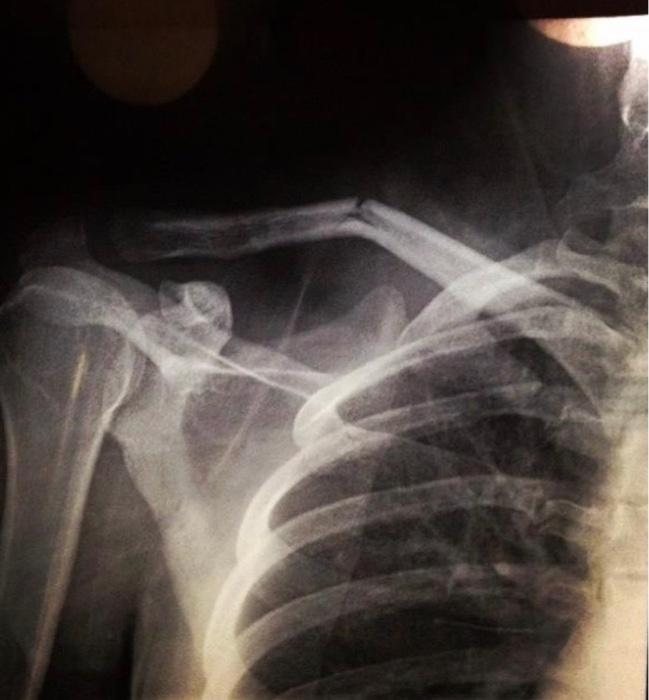

FOOSH or direct fall on the shoulder

clavicle fracture most common mechanism

drop

in a clavicle fracture, the shoulder will ____ because the trapezius cannot lift the lateral fragment to compensate for the sternocleidomastoid pulling the medial fragment superior

clavicle fracture

SCM pulls medial fragment superior in the mechanism of this injury

clavicle fractures

trapezius can’t lift the lateral fragment causing the shoulder drop in to this clavicle

greenstick fracture is this type of fracture, most commonly found in children